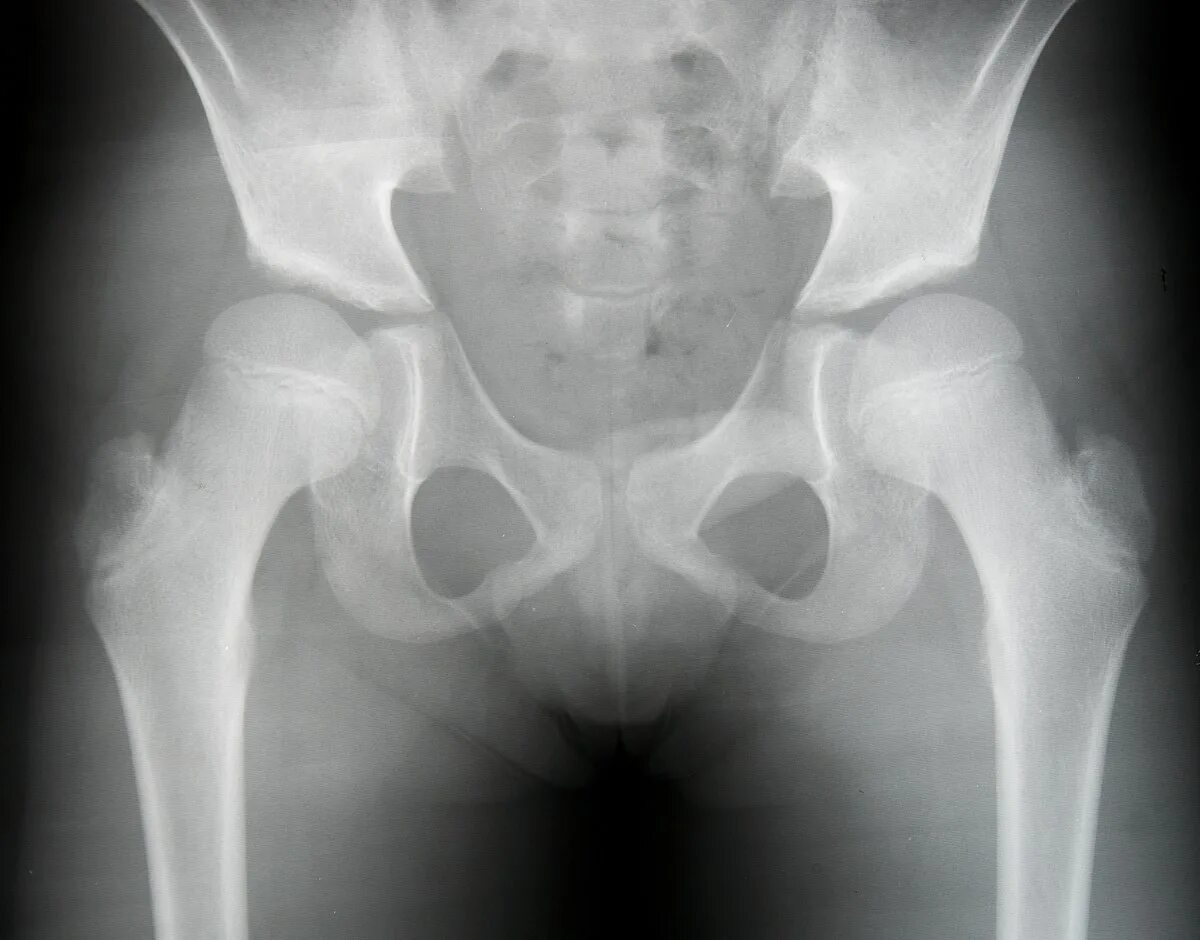

Тазобедренного сустава у детей